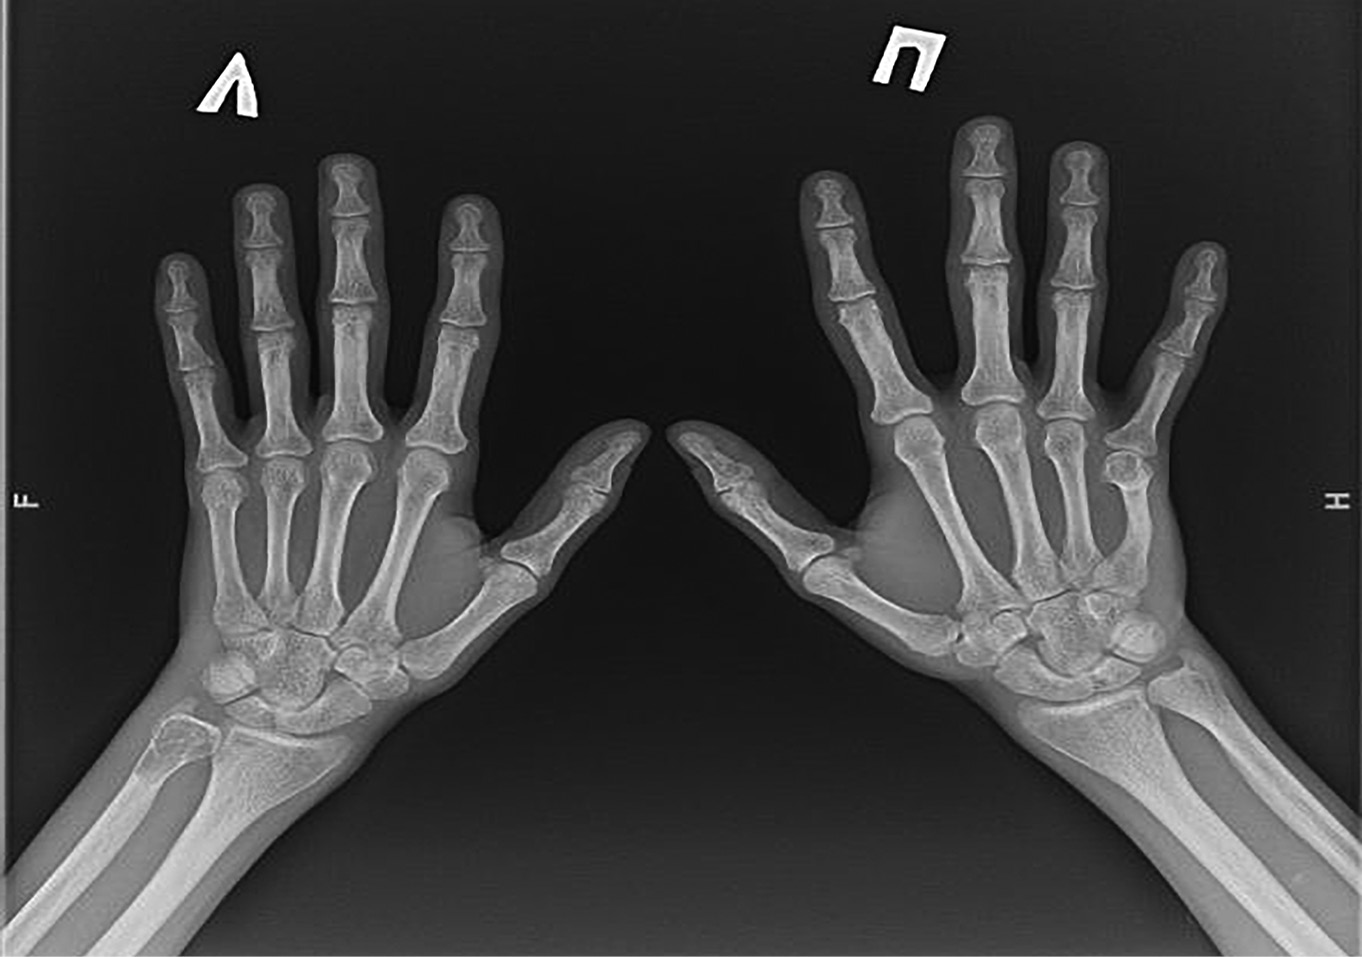

Рисунок 6. Рентгенография кистей с лучезапястными суставами. Диффузное снижение плотности костей, кистовидно-дистрофическая перестройка структуры дистального эпиметафиза левой локтевой кости с деструкциями от 3,9 мм до 10, 7 мм на фоне локальной псевдобуллизации. Справа — ульнарная девиация диафиза 5-й пястной кости с консолидированным переломом в средней трети, деформация с остеодистрофической перестройкой структуры головки и субкапитальной зоны. Перестроечные переломы в стадии консолидации диафизов 3-й и 4-й пястных костей правой кисти по медиальным поверхностям. Формирующиеся кисты в дистальных метаэпифизарных зонах лучевых костей с обеих сторон от 1 до 3 мм, а также в шиловидной зоне дистального эпифиза правой локтевой кости и в телах ладьевидной и полулунной костей правой кисти (0,5–2 мм).